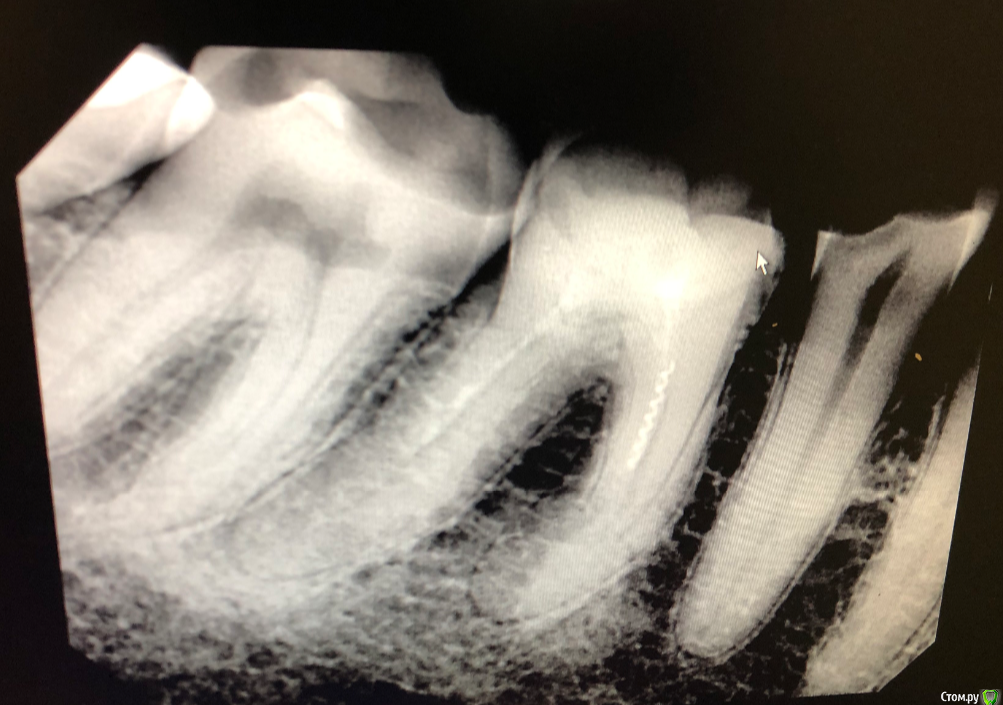

korkor Опубликовано 30 января, 2020 Поделиться Опубликовано 30 января, 2020 (изменено) Недавно заболел зуб. Болел после горячего. Потом просто стал болеть, даже проснулся ночью как-то от боли.Был у стоматолога. Она начала лечить зуб с одним каналом 29 (на фото он правее), так как там кариес был и дырка довольна большая. Рядом с ним 30 (левее) зуб мне лечили лет 10 назад. Сначала стоматолог говорила, что канал до конца недолечили, так как на снимке не видно, плюс инструмент в канале. Но так как у меня одна стенка зуба вся темно-коричневая (давно начал темнеть постепенно, сейчас весь темный), скорее всего там резицин-формалин. Рядом с ним зуб 31 (еще правее), сказала, что якобы может быть трещина в корню посередине зуба (на еще одном снимке там якобы темное уплотнение под корнем). И последний зуб мудрости (32) - там часть зуба откололась.Пролечили мне 29-й зуб с одним каналом. Но боль то есть, то нету. боль в основном ноющая, один день вообще ее нету, на другой опять есть, но слабее, чем была. 1. Помогите разобраться какой зуб может болеть и ответить на вопрос правильно ли мне удалили нерв в 29-м зубе?2. Возможно ли запломбировать 32-й зуб, коренной без удаления нерва? И если нельзя, то что лучше - удалять зуб или прочистить каналы и запломбировать?3. Что посоветуете делать с 30-м зубом (коричневый) и возможна ли боль от трещины (и есть ли трещина) в 31-м зубе? Изменено 30 января, 2020 пользователем korkor Ссылка на комментарий